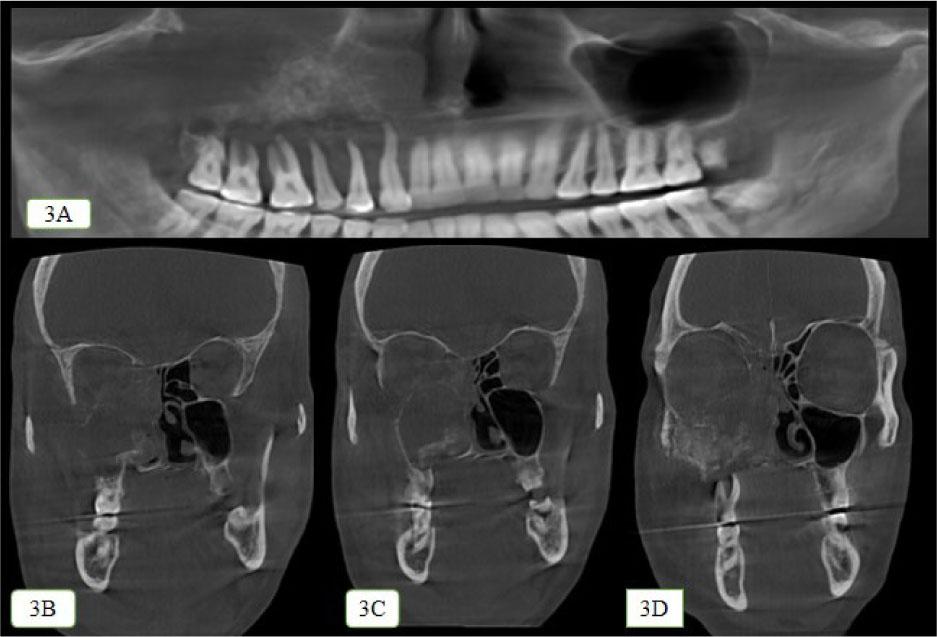

Radiographic investigation by cone beam computed tomography revealed an ill-defined mixed radiolucent radiopaque lesion in the right maxilla, extending mediolaterally from nasal septum to zygoma and superoinferiorly from right orbit to maxillary alveolus and palate along with destruction of alveolar bone, floor, medial wall, and lateral wall of right maxillary sinus as seen in Figure 3A–3D.

CBCT images showing the radiographic presentation of the lesion. 3A: Panoramic reconstructed image showing an ill-defined mixed radiolucent radiopaque lesion in the right maxilla, extending mediolaterally from nasal septum to zygoma and superoinferiorly from right orbit to maxillary alveolus and palate along with bone loss present around 13–18 region. 3B, 3C, 3D: Axial section showing the destruction of the floor of right orbit, anterolateral, and posterolateral wall of right maxillary sinus and nasal septum.